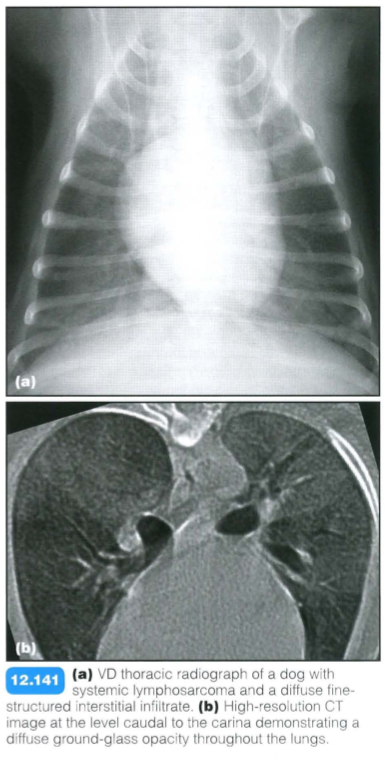

Multicentric lymphoma

Radiographic findings:

An interstitial pattern with lymphadenopathy is very suggestive of lymphoma, with the other main differential diagnosis being fungal pneumonia.

Radiographic diagnoisis is usually sufficient. CT may be performed for other reasons and typical features should be recognized: